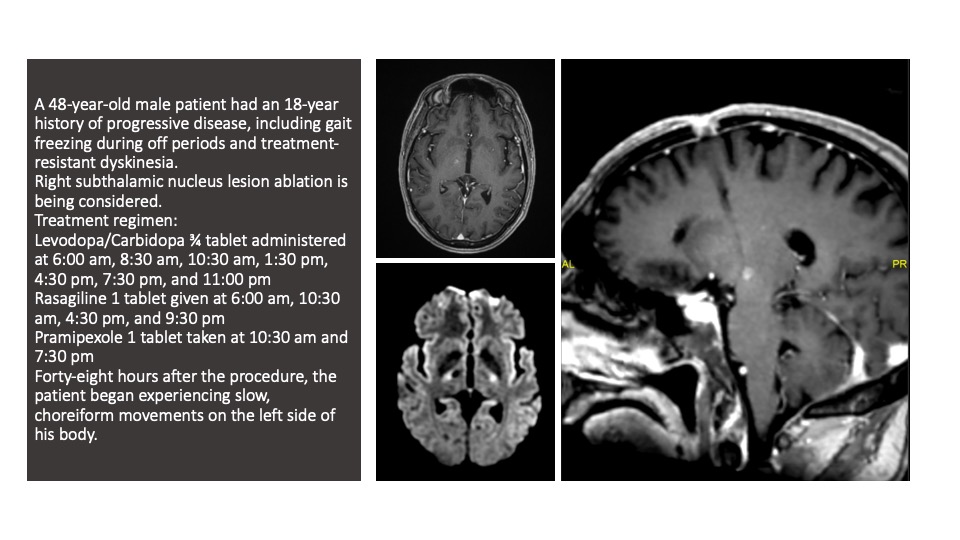

Results: Patients who underwent STN-DBS showed improvement in motor symptoms and quality of life but presented challenges in programming and side effects such as dyskinesias and neuropsychiatric symptoms. One patient who underwent ablative surgery developed “brittle dyskinesia” postoperatively, requiring pharmacological adjustments. Ablative surgery provided symptomatic relief with reduced medication requirements, though some patients experienced transient movement disorders. Our complication rates were consistent with existing literature.

Caso of “brittle dyskinesia”